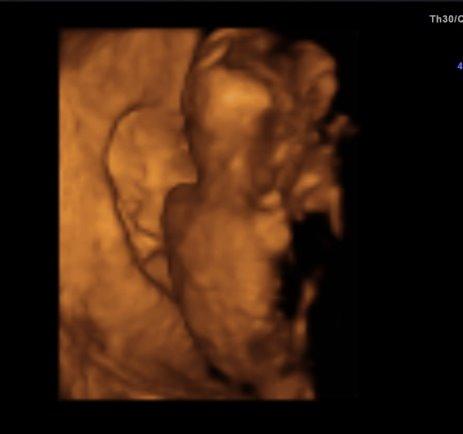

Hallihallo, war ja heute zur VU und wollte euch noch berichten. Soweit ist alles in Ordnung, nur das ich abgenommen habe hat meiner Ärztin nicht gefallen. Ist doch nur 1 kg Baby wiegt 170 g, die Gesamtlänge weiß ich leider nicht genau, laut FÄ richtet man sich da jetzt nach der SSW, also 17cm. Sie hat alles einzeln gemessen, Kopfdurchmesser, Oberschenkel und Bauchdurchmesser und dies entspricht 16+5, ich bin 16+4. Urin okay, Blutruck auch. Zum Geschlecht hat sie sich nicht 100%ig geäußert, da lag die Nabelschnur ungünstig. Schade, schade, aber einen kleinen Verdacht gab es schon, na mal sehen ob sich dieser bei der nächsten VU am 2.11. bestätigt Nun sind es wieder 4 lange Wochen bis dahin Einige Bilder gab es auch, die sind aber diesmal nicht so schön, da das kleine uns den Rücken zugedreht hatte. Naja, ein schöner Rücken kann auch entzücken Das von meiner Seite, hier noch ein Bild.